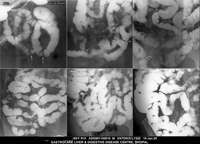

Section: ENTEROCLYSIS

Total: 205 Cases